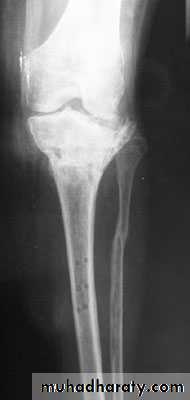

Delayed union and non union :When the fracture takes more time than expected to unite then it is delayed union

When the fracture fail to unite . For diagnosis of non union , 6 months of follow up should pass without clinical and\or radiological signs of union.

diagnosis

Delayed union : fracture tenderness persist , fracture line in the xray with very little or no callus

Non union : pain diminished , movement in the fracture site (pseudarthrosis or pseudojoint ) , xray show atrophic or hypertrophic bone ends

Treatment :

Delayed union : look for and treat the cause .Non union : treated mainly by surgical fixation with bone graft ( in Atrophic non union or without bone graft in cased of hypertrophic

Non union.